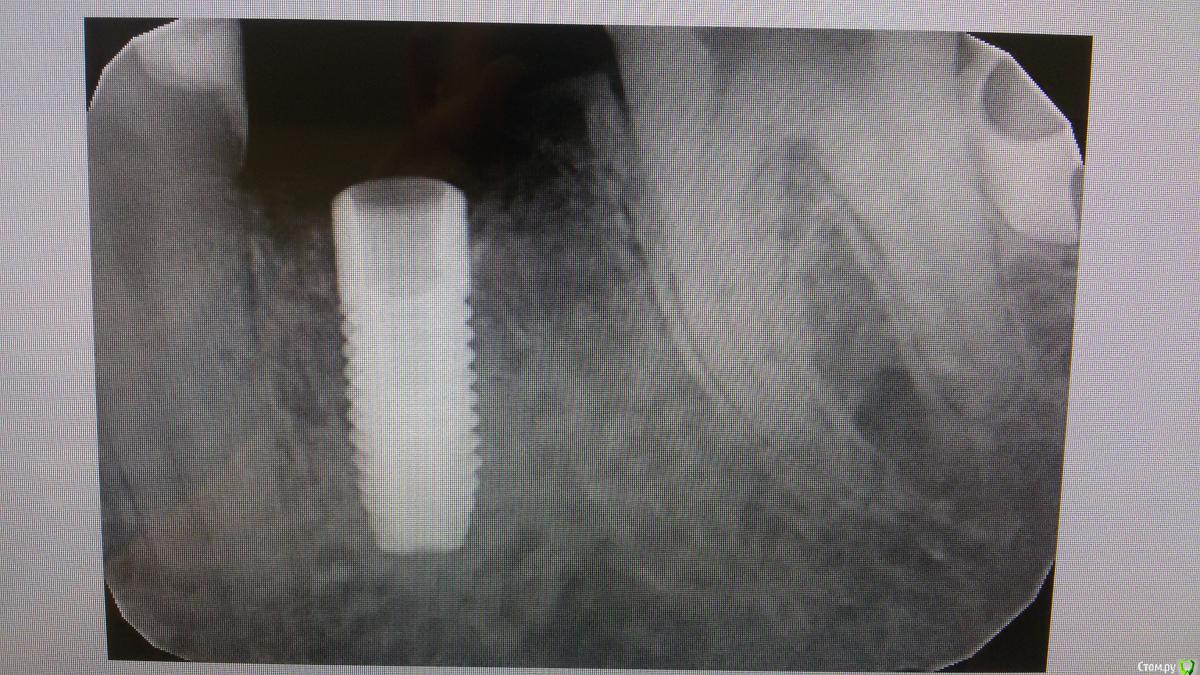

El_cucuy Опубликовано 22 января, 2020 Поделиться Опубликовано 22 января, 2020 (изменено) 1) поставить низкую заглушку, подшить сверху трансплантат под лоскутки 2) не делать ничего до интеграции, решать вопросы на втором этапе Доброго времени суток , доктора . По состоянию на 20 декабря , вот такая картина , нужно ли подсаживать трансплантат? Изменено 22 января, 2020 пользователем El_cucuy Ссылка на комментарий

El_cucuy Опубликовано 22 января, 2020 Поделиться Опубликовано 22 января, 2020 (изменено) нужны фото. И создавайте свои темы, а не засоряйте чужиеТот же кейс , добавил спустя 2 месяца Изменено 22 января, 2020 пользователем El_cucuy Ссылка на комментарий

Дмитрий Л. Опубликовано 26 января, 2020 Поделиться Опубликовано 26 января, 2020 Я бы не подсаживал, вроде 3 мм есть. 1 Ссылка на комментарий

red_butler Опубликовано 26 января, 2020 Поделиться Опубликовано 26 января, 2020 не вижу смысла работать с десной Ссылка на комментарий